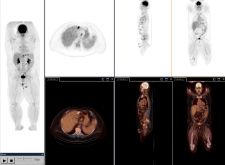

PET/CT in molecular imaging takes a 'photograph' of biological targets or pathways in the body for 'personalized medicine.' Photo courtesy of Siemens.

Over the next 10 years, the hybrid PET/CT modality is expected to surpass dedicated PET devices in terms of adoption, as the combined functional and anatomical information produced by the hybrid has proven increasingly beneficial in oncology and cardiology. PET/CT will also play an important role in the future of molecular imaging, which aims to “photograph” biological targets or pathways in the body for “personalized medicine,” which will eventually provide patient-specific information that allows clinicians to tailor the treatment of disease. These developments have charged the leading PET/CT manufacturers, GE Healthcare, Siemens, Hitachi and Philips, with enhancing image quality in the hybrid – particularly in PET. What is intriguing is that each manufacturer is approaching this challenge in its own way.